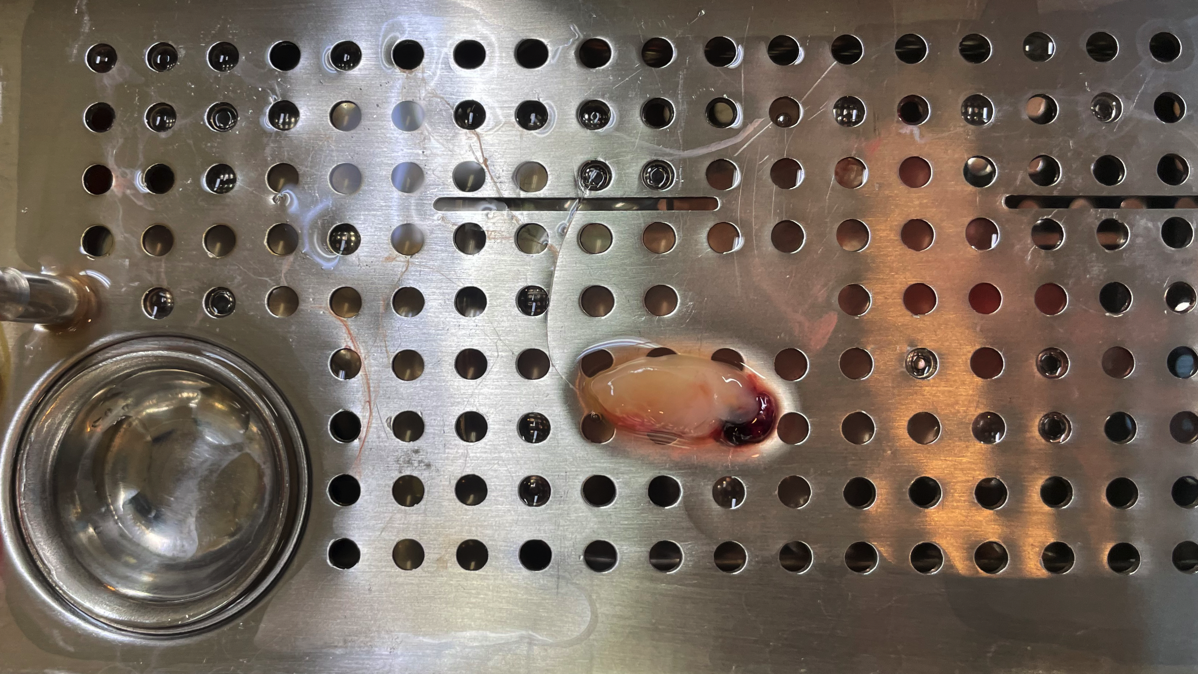

傷を早く治す術後の痛みが少ないPRFとPRP

PRFとPRPは再生医療の1つです。

処置直前に採血し血液を加工する事で、再生因子が豊富な加工物が得られます。

創傷治癒では再生因子が促進するので、早期の治癒が期待されます。

PRFには白血球も豊富に含まれるので、術後感染が生じにくいです。

また、術後疼痛が少ないです。

当院のPRFおよびPRPには、成長因子などの添加物は一切入っていません。

抜歯後の歯槽骨を保存するためには良い方法です。

歯槽骨を十分に残す利点は、かみ合わせや咀嚼の障害が回避できる、あるいは補綴物の機能および審美障害を防ぐことができることです。

処置直前に採血し血液を加工する事で、再生因子が豊富な加工物が得られます。

創傷治癒では再生因子が促進するので、早期の治癒が期待されます。

PRFには白血球も豊富に含まれるので、術後感染が生じにくいです。

また、術後疼痛が少ないです。

当院のPRFおよびPRPには、成長因子などの添加物は一切入っていません。

抜歯後の歯槽骨を保存するためには良い方法です。

歯槽骨を十分に残す利点は、かみ合わせや咀嚼の障害が回避できる、あるいは補綴物の機能および審美障害を防ぐことができることです。